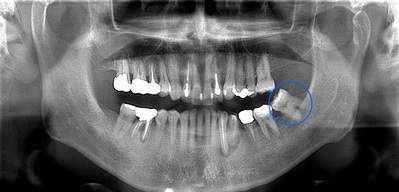

右下の親知らずが疼く症例

- 抜歯前写真(レントゲン)

- 抜去歯の写真(CT画像)

| 年齢 | 30代・女性 |

|---|---|

| 主訴 | 右下親知らずが疼く |

| 親知らずの生え方 | 横向きに生えている |

| 抜歯時間 | 40分 |

| 費用 | 約8,000円(保険診療、CT代含む) |

| 抜歯内容 | 右下の親知らずは横向きに生えて埋まっているため、麻酔をし親知らずの奥に切開を入れて歯ぐきを開き、歯を囲んでいる骨を削り歯の頭部分を割って出してから、残った根の部分を取り出して抜歯は終了しました。 歯ぐきを切った部分は糸で縫っています。このケースでは根の先端が神経に近く麻痺のリスクがありましたが事前にCTを撮影し、神経との位置関係を確認していたため、麻痺が残ることはありませんでした。 約1週間後に糸取りを行い、その際も多少の痛みや腫れはありましたが後日その痛みも無くなりました。 |